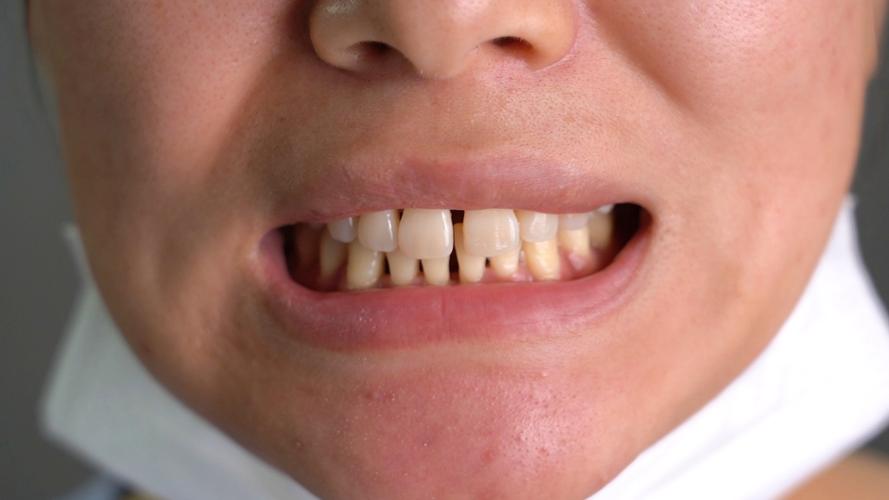

正畸下前牙骨开裂的临床表现

骨开裂的临床表现因裂缝程度、位置及是否合并感染而异,早期症状可能不明显,易被忽视,随病情进展可出现以下特征:

牙齿症状

- 松动度异常:患牙出现Ⅰ-Ⅲ度松动,尤其是垂直向或侧向松动,超出正常牙齿生理动度范围。

- 咬合不适:咬硬物时出现疼痛、酸软感,或感觉牙齿“浮起”,严重时可出现咬合干扰。

牙周及牙龈症状

- 牙龈退缩:骨开裂常伴随牙槽骨高度降低,导致牙龈缘向根方退缩,牙根部分暴露,冷热刺激敏感。